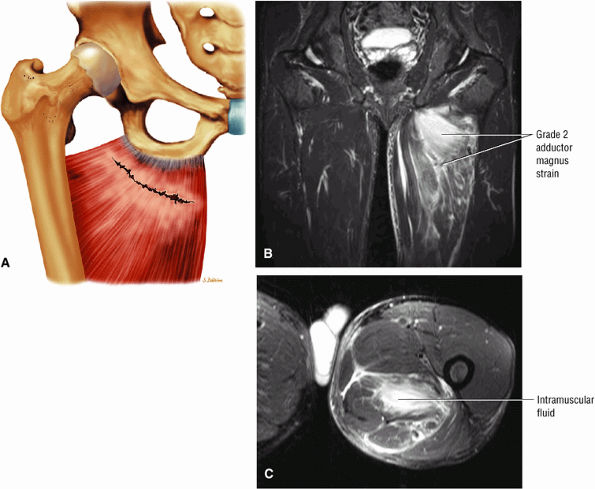

Grade 1: Minimal disruption of the musculotendinous junction (Fig. 3.106). Clinically, a grade 1 strain may simply result in a muscle spasm or cramp.

Grade 2: A partial tear with some intact musculotendinous fibers (Fig. 3.107). Clinically, there is discomfort during sports activity or training, but it usually resolves with rest.

Grade 3: Complete rupture of the MTU (Fig. 3.108)

-

Grade 2: Hyperintense hemorrhage with tearing and disruption of up to 50% of the muscle fibers. Interstitial hyperintensity with focal hyperintensity represents hemorrhage in the muscle belly with or without intramuscular fluid (Figs. 3.111 and 3.112). A hyperintense focal defect and partial retraction of muscle fibers may also be visualized. Associated myotendinous and tendinous injuries as well as hyperintensity and interruption and widening of the MTU are also found.